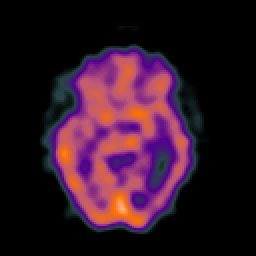

SPECT TC Study #4 -- Slice #25

[Home][Help][Clinical][Tour 1][Tour 2][Tour 3] Slice 25